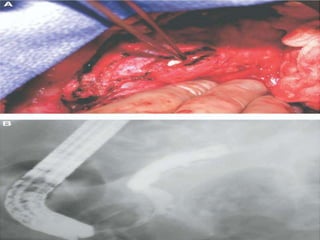

• #27 Lpj id calculi.ERCP dilated duct cut off due to caluli

• #30 Completed lpj

• #35 Two layered end to side PJ,5 fr stent,complete.